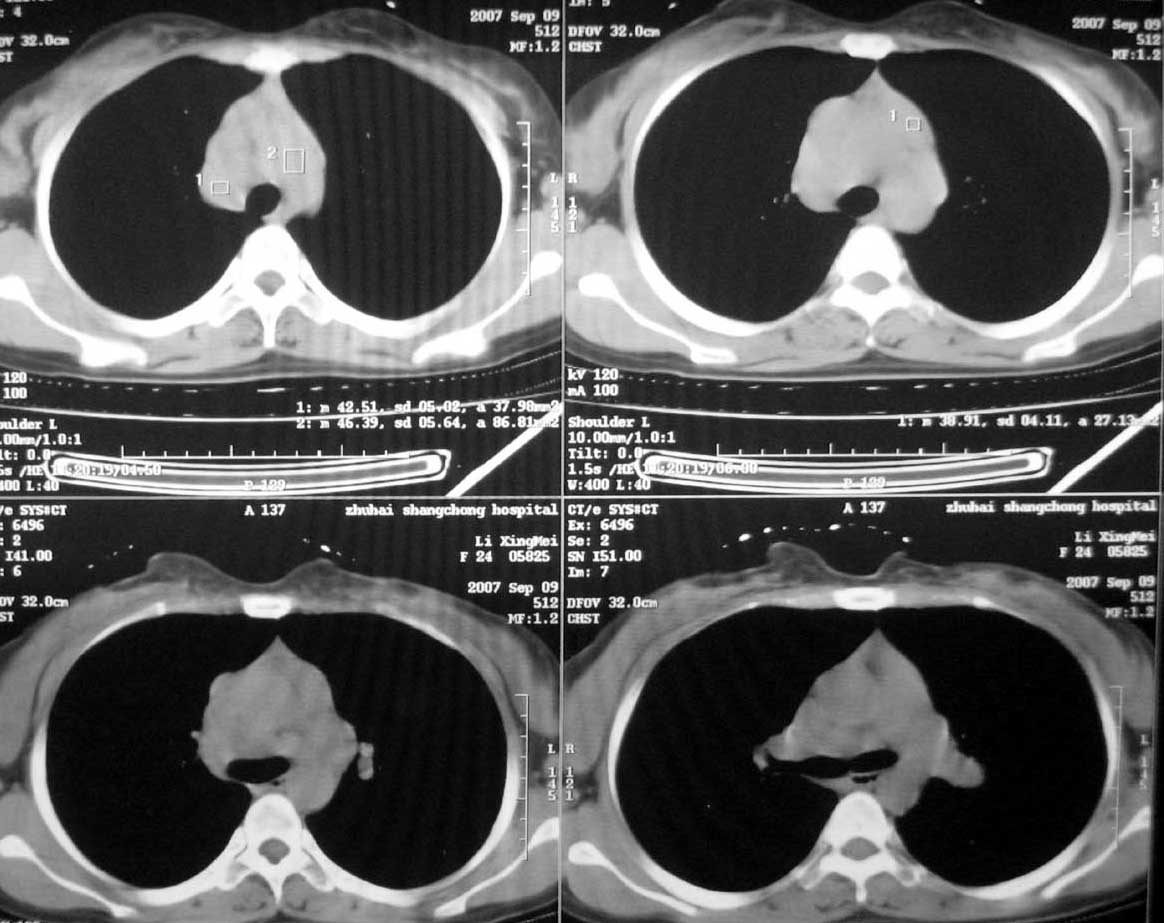

以下是引用qiuleiyu在2007-9-14 19:12:00的发言:[br]纵隔(气管旁组\\隆突下\\主动脉旁组\\血管前组)及肺门淋巴肿大,边界欠清.密度均匀,内无明确钙化.[br]结合临床症状考虑;结节病可能大.[br]鉴别;1,淋巴瘤,可有全身浅表淋巴肿大,肝脾大,发热等.肿大淋巴主要为气管旁组及血管前组及主动脉旁组,肺门肿大不明显.典型者为冰冻纵隔.[br] 2,转移瘤;多见于肺癌,按淋巴链分布肿大,单侧肿大多见,常可见坏死.[br] 3,castlemans;增强后明显血管样强化.内部可有分支状钙化,蜘蛛状瘢痕.周边可有粗大血管.[br] 4,结核;67%有肺部结核灶,肿大淋巴结节,内部可有钙化,增强环状或分格样强化.